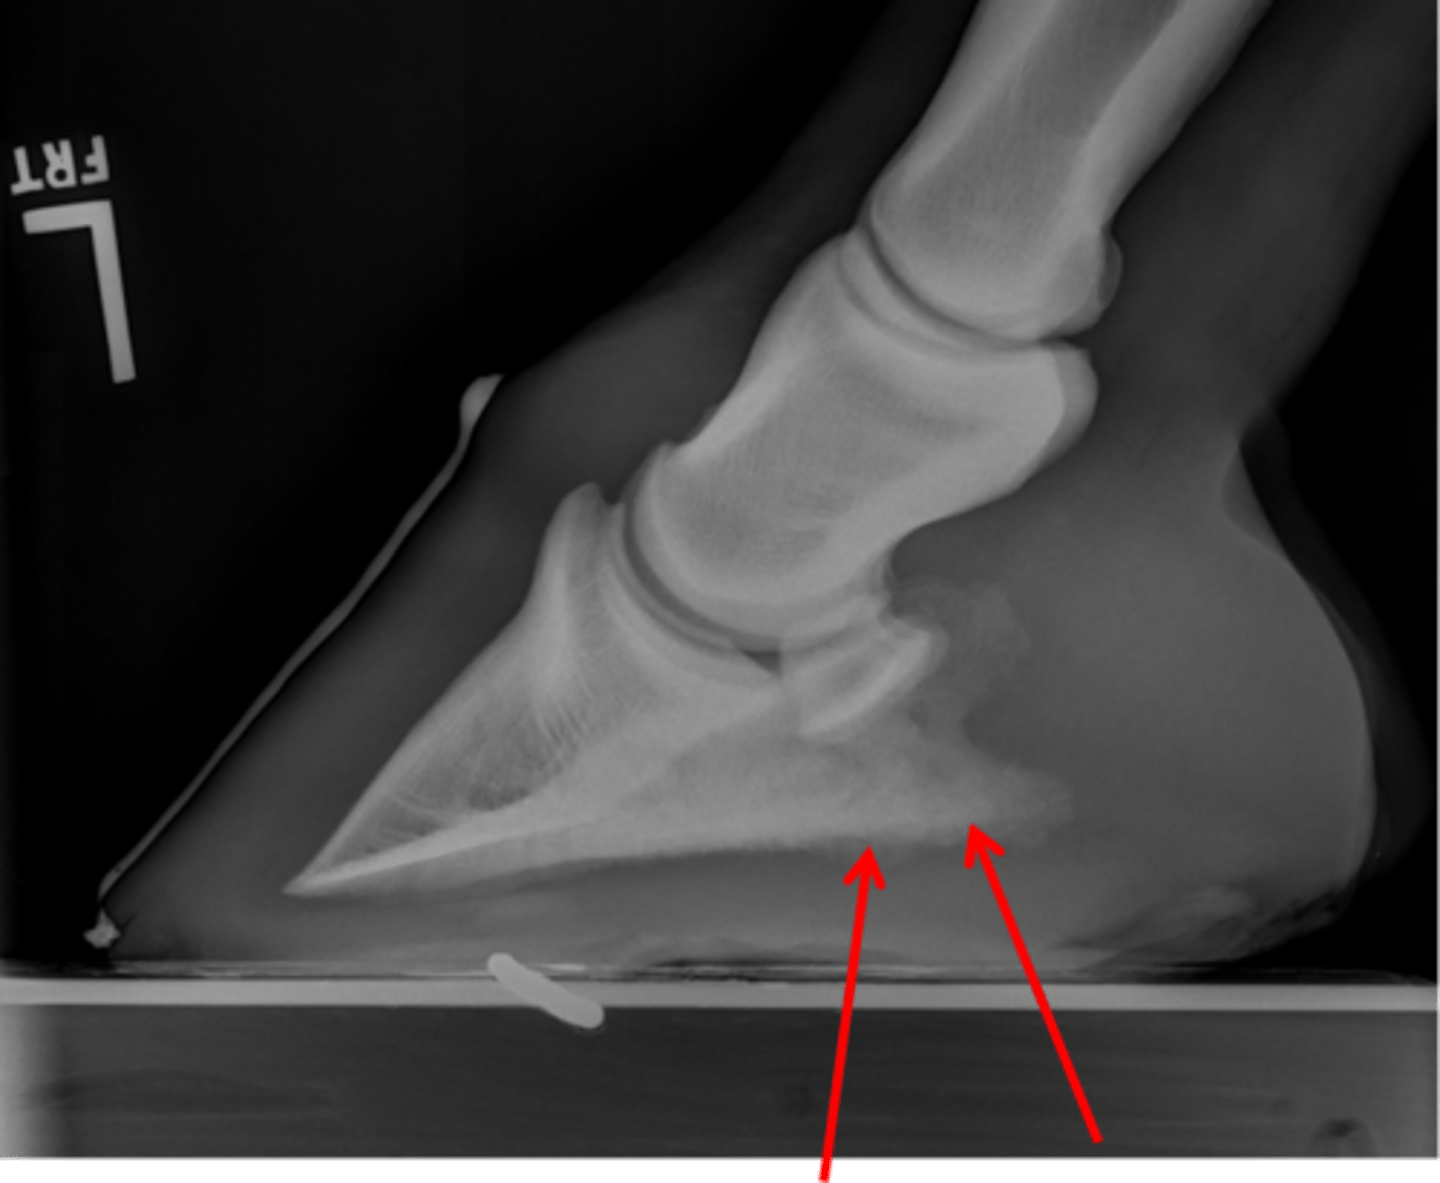

Coffin bone (P3)

Navicular bone

Coffin joint

Short pastern (P2)

What view is this?

Coffin bone

Navicular bone

Pastern joint, LM

ID joint and view

Pastern joint, DP

ID joint and view